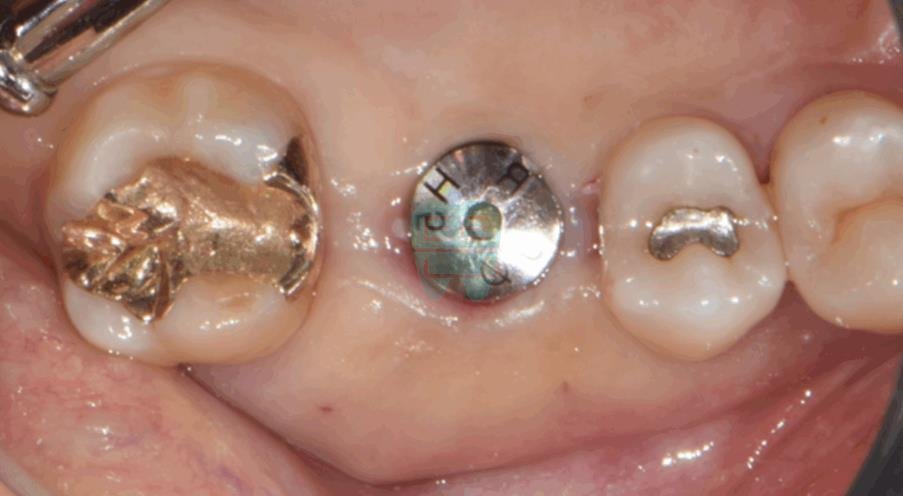

**Initial Intraoral Photo** — The patient presented with a missing tooth requiring implant treatment.

**Post-operative Intraoral Photo** — Clean surgical site with no incision.

**Final Prosthesis Intraoral Photo**

Pre-operative intraoral photo showing the missing tooth site